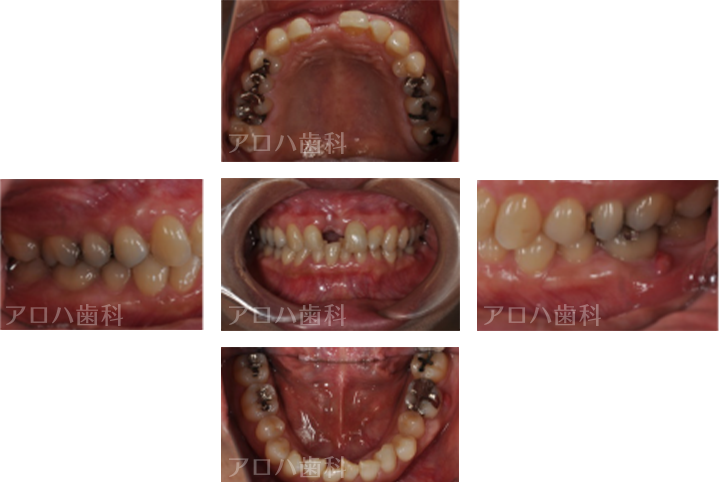

CASE02/30代女性

初診時

| 主訴 | 右の前歯が折れた、矯正治療もしたい |

| 治療内容 | 転んで前歯を失った方です。 下の前歯もガタガタが気になるとのことで、矯正治療と並行してインプラント治療を行いました。 治療後3年間経過していますが、ほとんど骨吸収なく順調な経過をたどっています。 |

| 治療期間 | 6か月 ※矯正治療期間は別途 |

| 治療費用 | 605,000円 ※矯正治療費用は別途 |

| 費用詳細 | ・サージカルガイド 55,000円 ・GBR 110,000円 ・インプラント手術+アバットメント+上部構造 440,000円 |